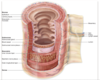

Layers of the GI tract1

Mucosa

epithelial lining

lamina propria (loose connective tissue)

muscularis mucosa

submucosa (dense connective tissue)

muscularis propria

serosa (loose connective tissue)

Layers of the GI tract pic